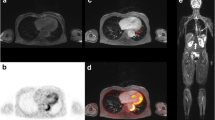

The image quality of [18F]FDG PET/MRI was rated in all cases as good (category 2) or excellent image quality (category 3). In [18F]FDG PET/CT, only a single scan was rated as diagnostic but image quality reduced (category 1) (see Table 3). This rating was based on multiple motion and breathing artefacts during CT acquisition. The analysis of diagnostic confidence in image quality showed no significant difference between the two groups. There were moderate interobserver agreements for [18F]FDG PET/MRI (κ = 0.366) and [18F]FDG PET/CT (κ = 0.578) for image quality. Figures 3 and 4 demonstrate representative [18F]FDG PET/CT and [18F]FDG PET/MR images from this study.

[18F]FDG PET/CT image showing an active aortitis with vessel wall thickening in sagittal reformatted CT angiography images (a) and [18F]FDG uptake at the aortic arch and the descending aorta (b). 3D volume rendering of the aorta shows no pathologic dilatation of the vessel (c). The tracer activity of 263MBq corresponding to 7.1 mSv and a DLP of 1625 mGy*cm corresponded to 24.375 mSv, and made up a total effective dose of 31.5 mSv

[18F]FDG PET/MR image of an inflammatory aortic aneurysm. Axial T1 vibe image after contrast shows the abdominal aortic aneurysm with vessel wall thickening and intraluminal thrombus formation (a). Fused images show pronounced [18F]FDG uptake within the thickened vessel wall as well (b, c). 3D rendering of the MR angiography shows the localized widening of the infrarenal aorta (d). The tracer activity of 289MBq corresponded to an effective dose of 7.8 mSv